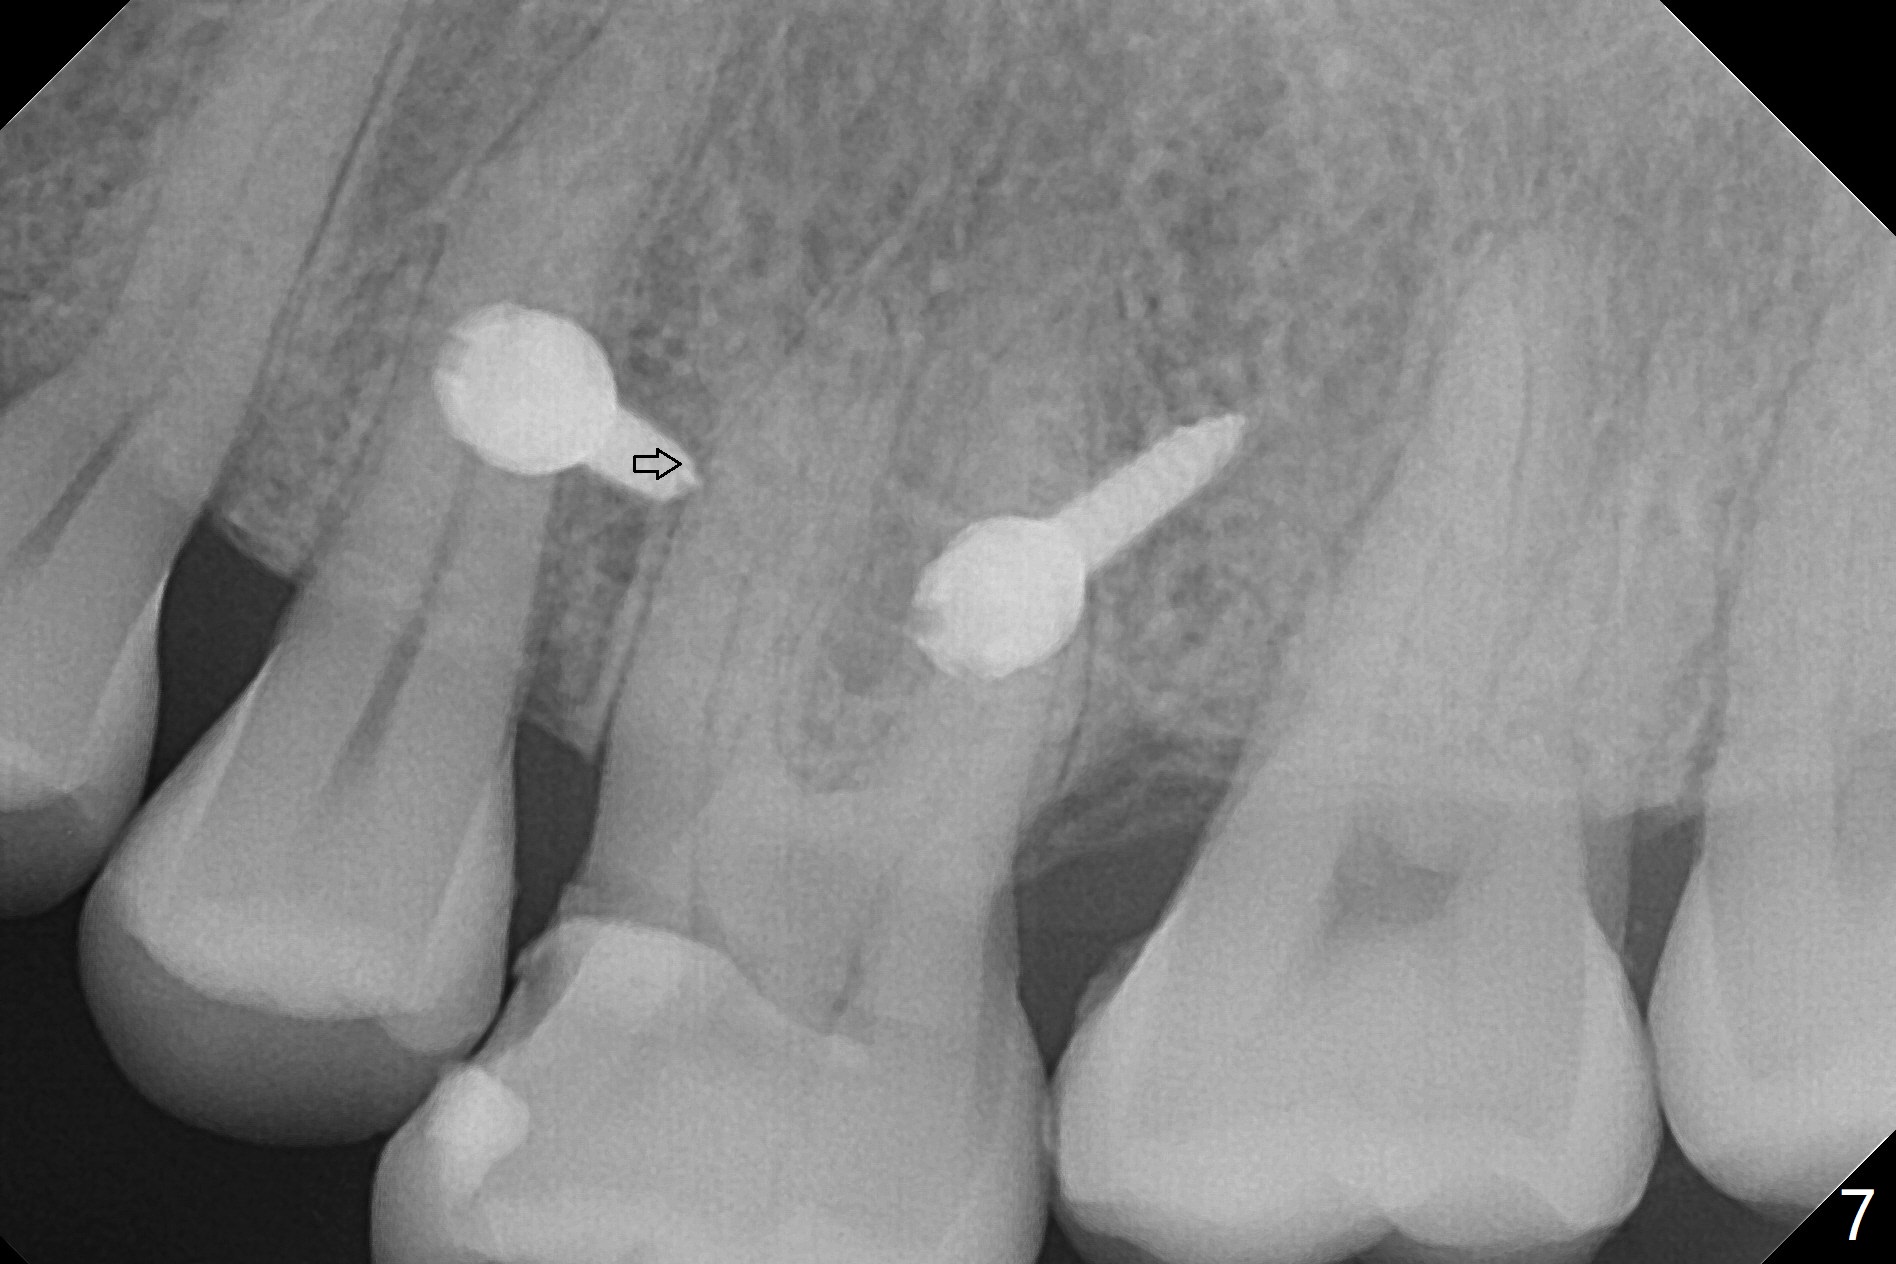

Fourteen days prior to implantation at #19 to replace a flipper (Fig.2), two minimplants are placed to intrude the supraerupted opposing tooth (#14, Fig.1). After use of minimal amount of local anesthetic (to keep proprioceptive in case root surface violation), the miniimplants are inserted ~ half of the length initially (Fig.3,4). The mesiobuccal (MB) one seems to be better positioned than the distopalatal (DP) one. When the implants are completely seated (Fig.5,6), three of PAs are taken, which suggests contact of the MB implant to the MB root of the tooth #14 (Fig.7 arrow). Immediately postop CT confirms approximation of MB and DP implants to the MB and P roots, respectively (Fig.8,9). The trajectory of these implants remain unchanged. Twelve days postop, the patient returns, uncomfortable with the palatal implant. After deep placement to bury the cuff (Fig.6) without local anesthesia (bone having no innervation), the patient feels better.